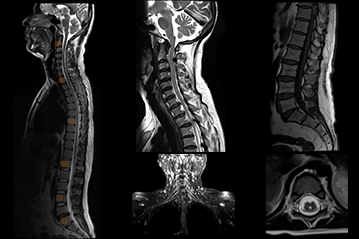

Clarity's high-quality imaging can be applied to a range of clinical neuro imaging.

MRA/MRV, DWI with multipe b-value, ADC and eADC, SWAPP (SWI), Tornado (motion correction), ASL, DTI, Single Voxel Spectroscopy, DCE - MRI

3D MERGE

Specifically crafted for imaging the neck and cervical spine, this technique aims to fully eliminate pulsation artifacts.